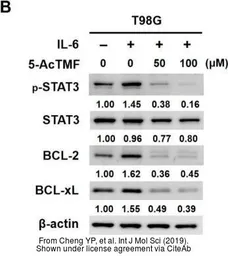

The data was published in the journal Int J Mol Sci in 2019. PMID: 31323961

The data was published in the journal Int J Mol Sci in 2019. PMID: 31323961

The data was published in the journal Int J Mol Sci in 2019. PMID: 31323961

The data was published in the journal Int J Mol Sci in 2019. PMID: 31323961